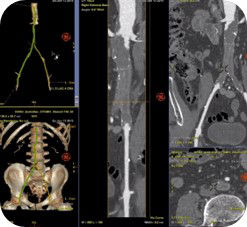

Die automatische Segmentierung von Knochen und Gefäßen und die Mittellinienverfolgung durch den Gefäßverschluss ermöglichen eine schnelle Planung anhand von präoperativen CT- oder MR-Bildern. Durch diese Kombination präoperativer CT- oder MR-Bilder mit Mittellinienverfolgung und Durchleuchtung in Echtzeit können Spezialisten außerordentlich gut sehen, wo die Rekanalisation vorgenommen werden muss und wo sich die Einstichstelle befindet, ohne die Kontrastmittelmenge erhöhen zu müssen.

Vessel ASSIST bietet eine präzise und einfache anatomische Segmentierung und genaue Gefäßquantifizierung anhand von 3D-Volumen. Zudem ermöglichen die erweiterte 3D-Roadmap und erweiterte Bildführungsfunktionen für die frontale und laterale Ebene das sichere Führen von Kathetern.